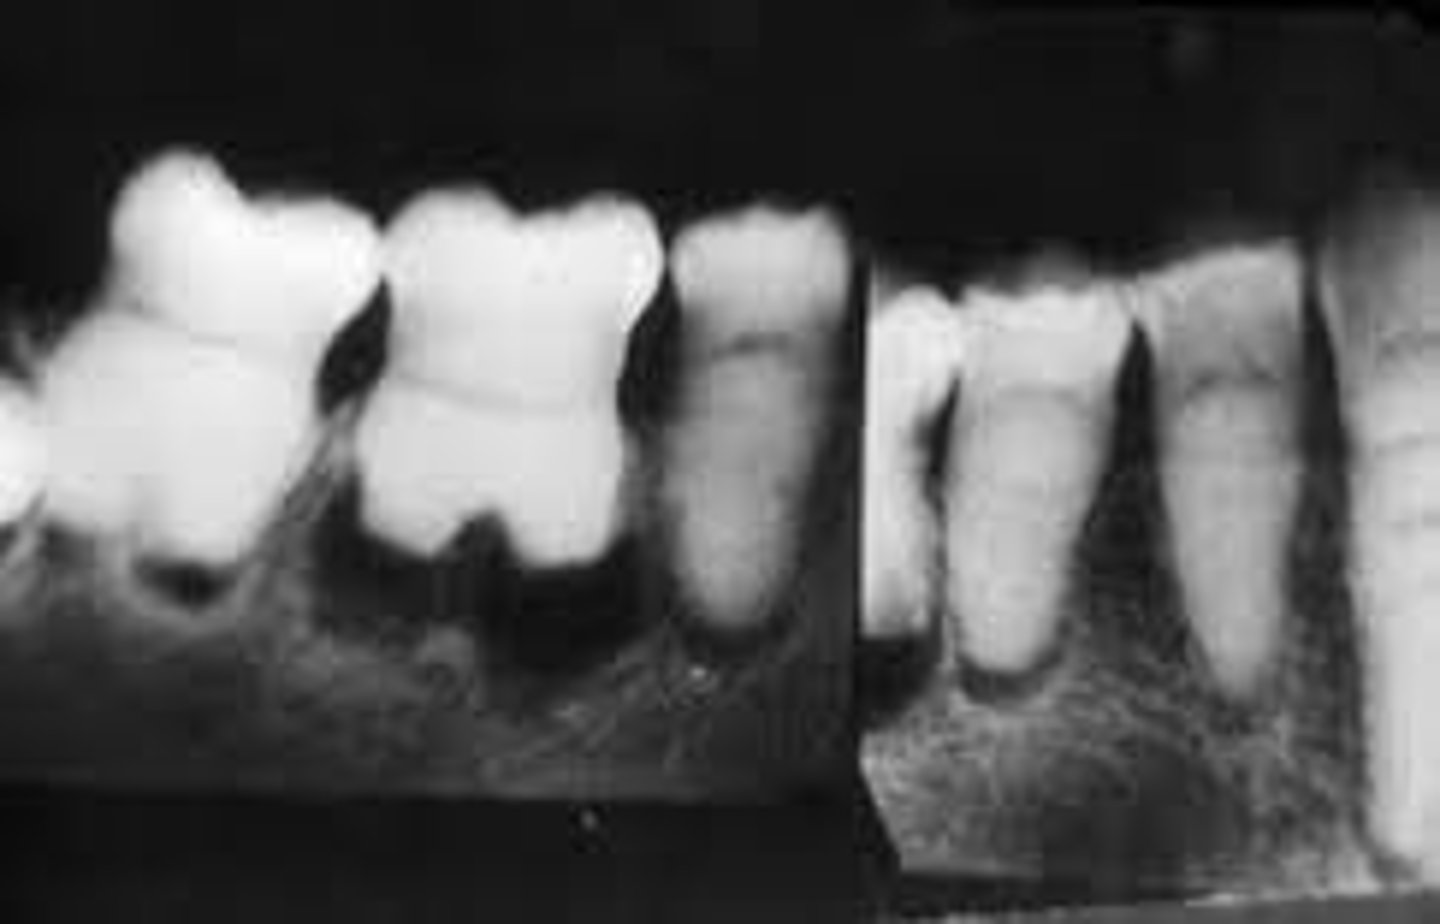

What type of dentin condition involves rootless teeth?

Dentin Dysplasia

Which type of Dentin Dysplasia has normal roots?

Type 2 Coronal